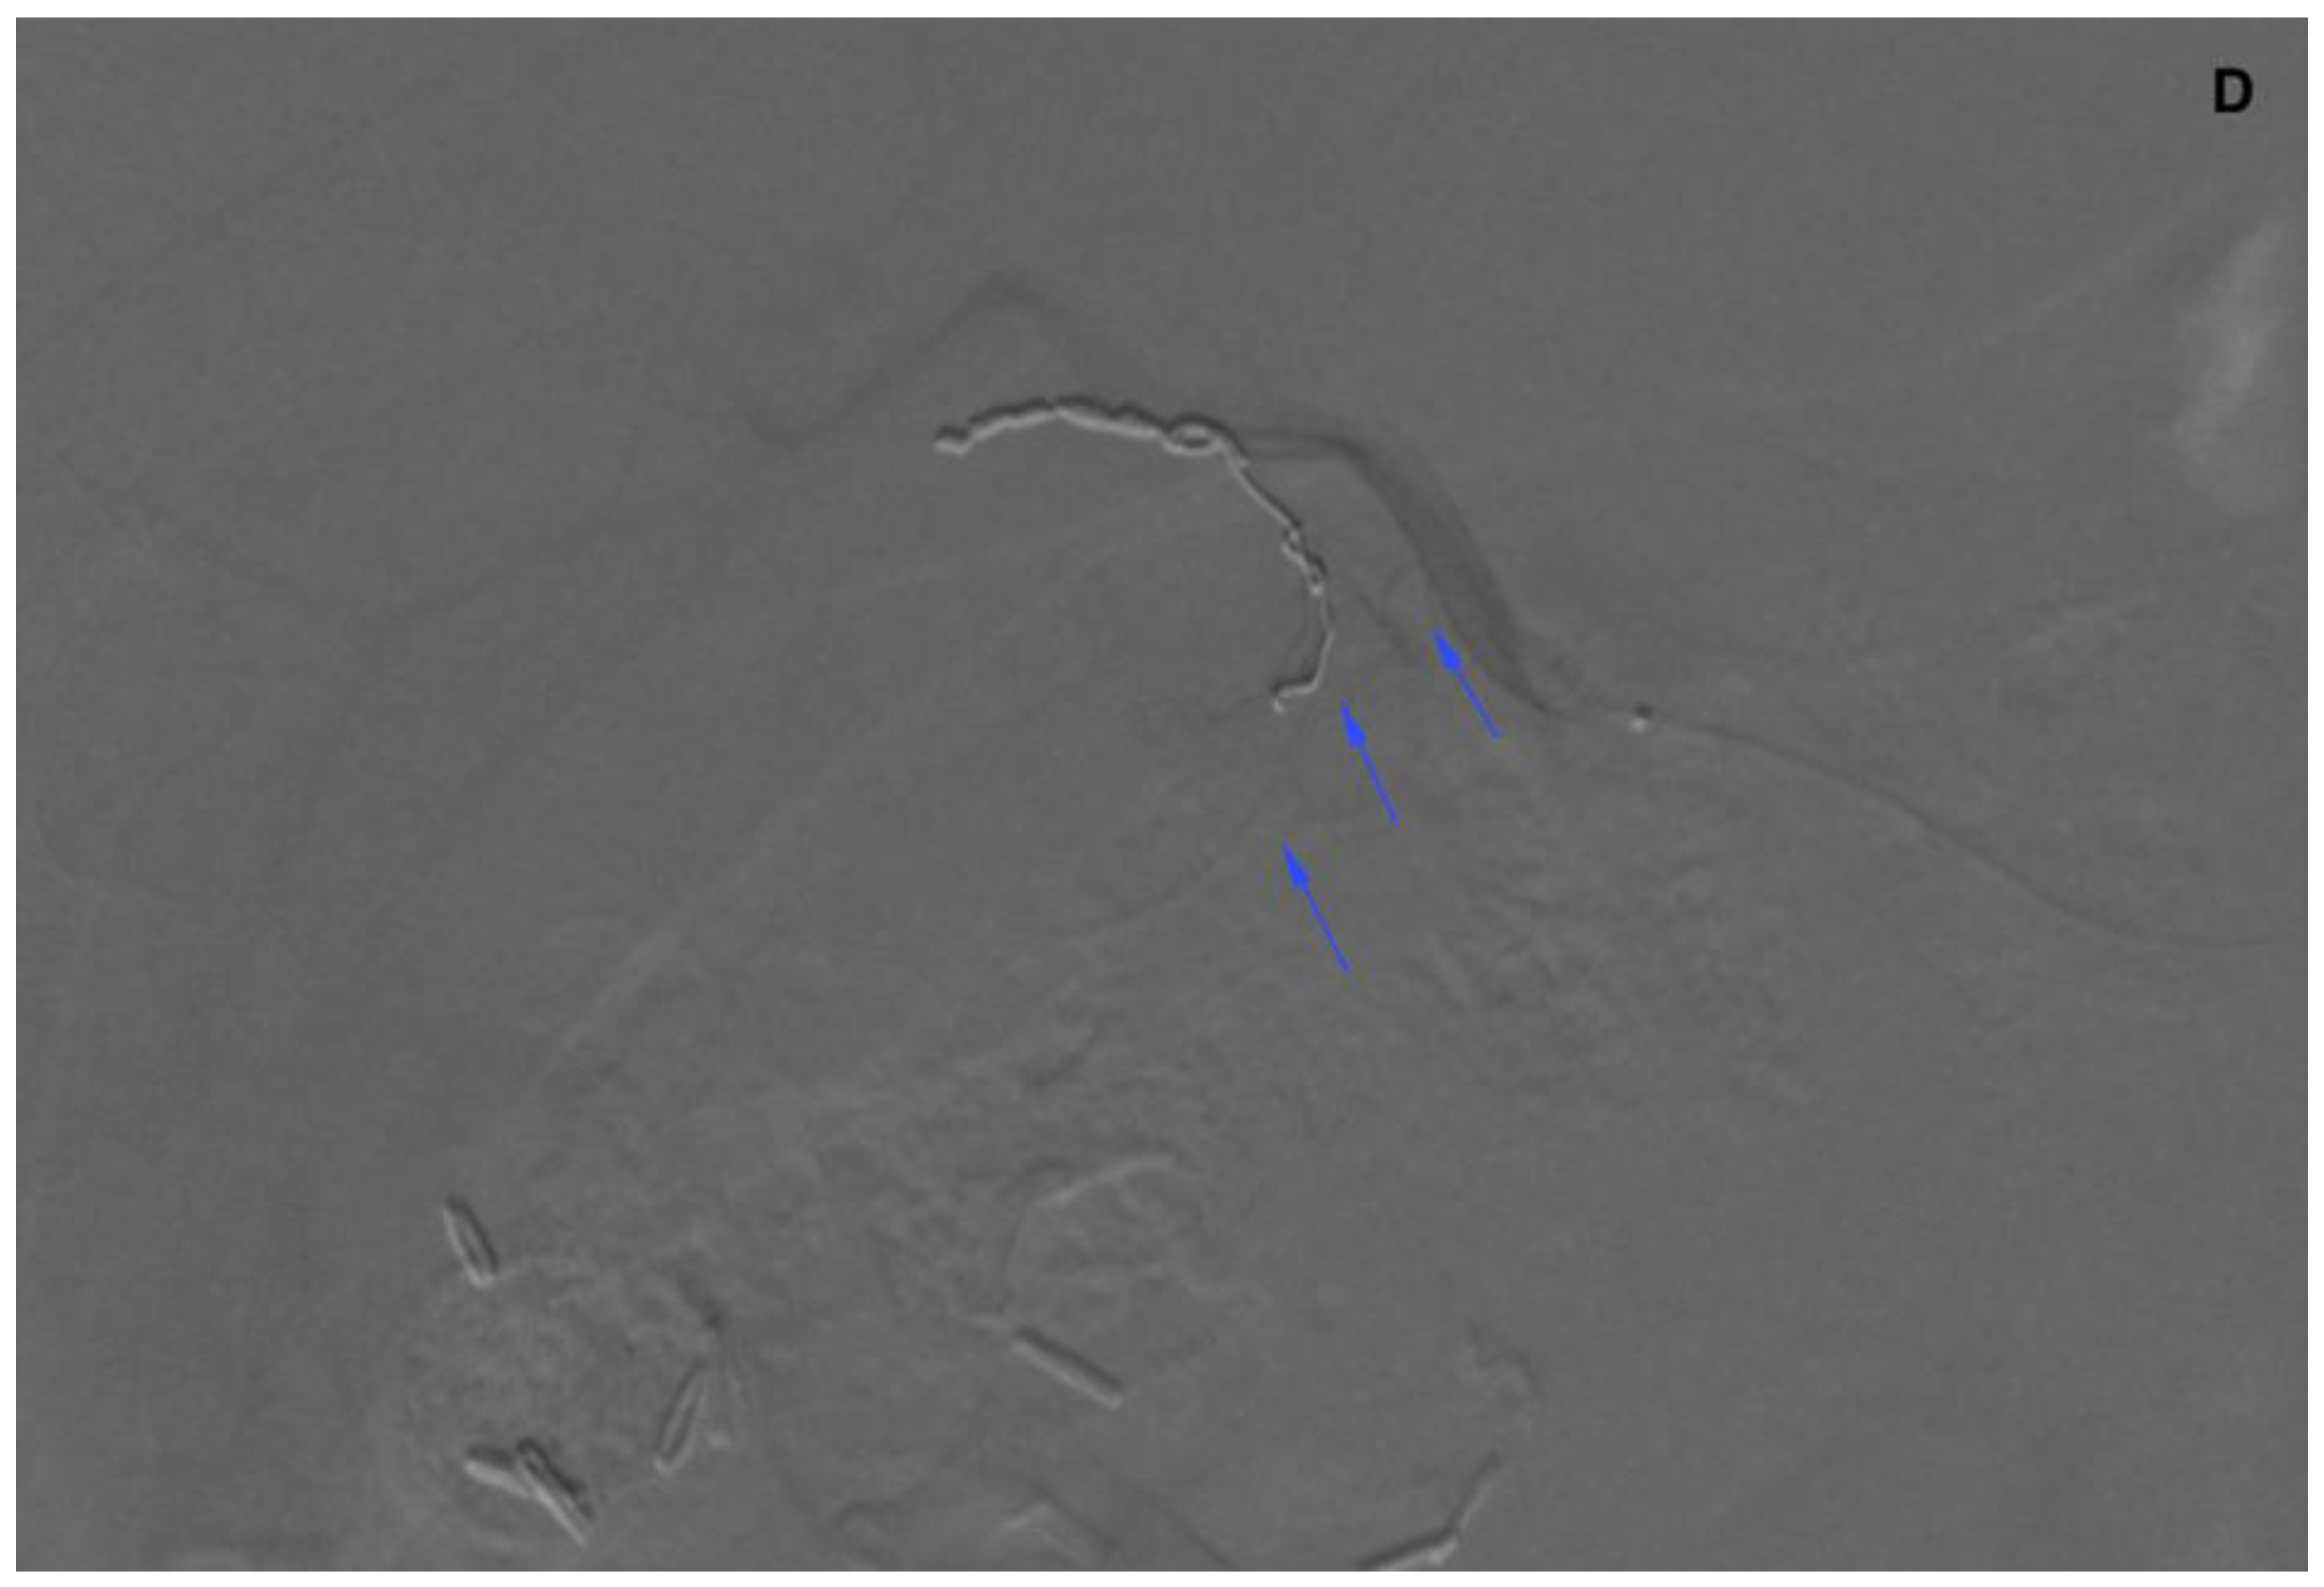

Figure 6.

(A) Angiogram of the left hepatic artery showing falciform artery travelling medially beyond the margin of the liver. (B) Its presence was confirmed on Dyna-CT and showed contrast enhancement of the abdominal wall (arrows) (C), and on SPECT/CT after 99mTc-MAA injection (D) (crosshairs).